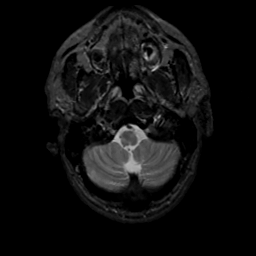

MR Study #10, April 28, 1991 -- Slice #5